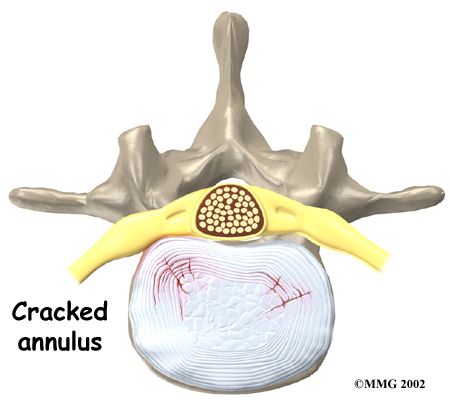

A disc is made of . The center, called the nucleus, is spongy. It provides most of the disc's ability to absorb shock. The nucleus is held in place by the annulus, a series of strong ligament rings surrounding it. Ligaments are connective tissues that attach bones to other bones.

Herniation occurs when the nucleus in the center of the disc pushes out of its normal space. The nucleus presses against the annulus, causing the disc to bulge outward. Sometimes the nucleus herniates completely through the annulus and squeezes out of the disc.

Although daily activities may cause the nucleus to press against the annulus, the body is normally able to withstand this pressure. However, as the annulus ages, it tends to . It is repaired with scar tissue. This process is known as degeneration. Over time, the annulus weakens, and the nucleus may begin to herniate (squeeze) through the damaged annulus. At first, the pressure bulges the annulus outward. Eventually, the nucleus may herniate completely through the outer ring of the disc.

Although daily activities may cause the nucleus to press against the annulus, the body is normally able to withstand this pressure. However, as the annulus ages, it tends to . It is repaired with scar tissue. This process is known as degeneration. Over time, the annulus weakens, and the nucleus may begin to herniate (squeeze) through the damaged annulus. At first, the pressure bulges the annulus outward. Eventually, the nucleus may herniate completely through the outer ring of the disc.

Many cases of lumbar disc herniation result from degenerative changes in the spine. The changes that eventually lead to a disc herniation produce symptoms gradually. At first, complaints may only be dull pain centered in the low back, pain that comes and goes over a period of a few years. Doctors think this is mainly from small tears in the annulus. Larger cracks in the annulus may spread pain into the buttocks or lower limbs.

Many cases of lumbar disc herniation result from degenerative changes in the spine. The changes that eventually lead to a disc herniation produce symptoms gradually. At first, complaints may only be dull pain centered in the low back, pain that comes and goes over a period of a few years. Doctors think this is mainly from small tears in the annulus. Larger cracks in the annulus may spread pain into the buttocks or lower limbs.